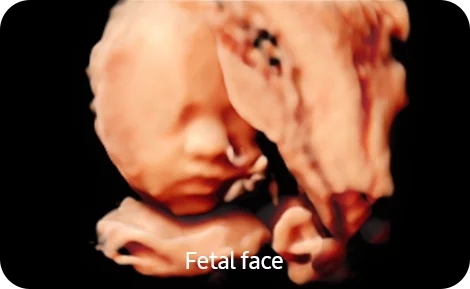

• Автоматическое измерение фетометрических показателей с помощью Biometry Assist

• Предустановленные параметры для различных триместров беременности

• Smart 4D- Модуль объемного сканирования в реальном времени Smart 4D с расширенным набором инструментов для обработки и представления объемного изображения;

• Realistic Vue- Модуль реконструкции объемного изображения с возможностью перемещения виртуального источника освещения Realistic Vue. Необходим модуль 4D;

• Crystal Vue- Модуль визуализации объемного изображения, с усиленной способностью к контрасту за счет использования различных степеней прозрачности и подсветки структур Crystal Vue;

• 5D NT- Модуль автоматического измерения ТВП и интракраниального пространства плода 5D NT в режиме объемного сканирования;

• 5D CNS+- Модуль автоматического получения 9 стандартных поскостей головного мозга плода и последующих автоматических измерений стандартных параметров фетометии головного мозга плода 5D CNS из объемных данных. Необходим модуль 4D. (CV1-8AD);

• 5D Heart Color- Модуль автоматического получения 9 стандартных плоскостей сердца плода из объемных данных STIC в соответствии с международными методическими рекомендациями с динамическим отображением кровотока 5D Heart Color. Необходим модуль 4D. (CV1-8AD, EV2-10A);